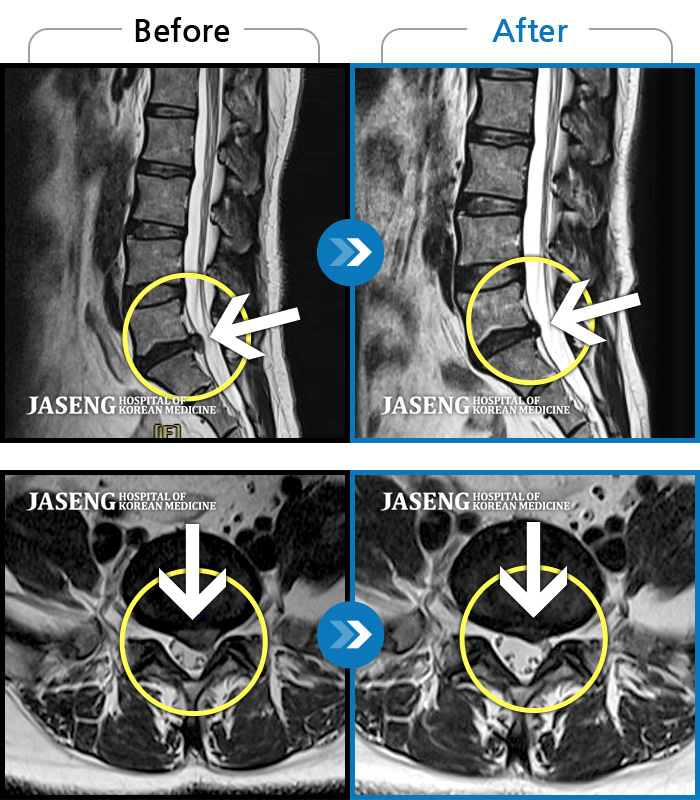

허리디스크

도움받은 사례

광주 · 장영우 원장

양측 허리의 묵직한 통증 및 기침 시 증상이 심화되어 내원하셨습니다.

촬영시기

2024.12.09 ~ 2025.05.24

2025.06.05